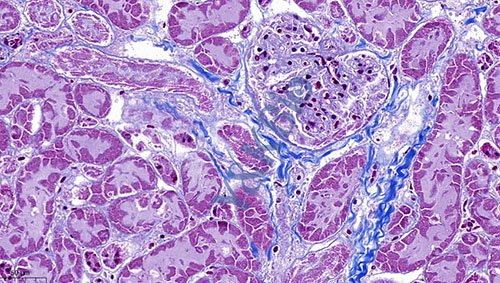

黑龙江Masson染色是病理染色服务中比较常见的一种,Masson染色用于胶原纤维和肌纤维的染色及鉴定;染色结果:胶原纤维呈蓝色、肌纤维呈红色、细胞核呈蓝黑色。